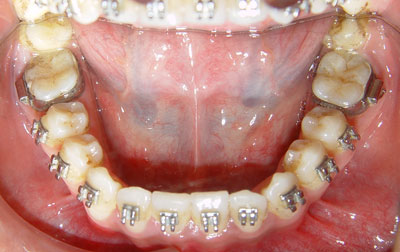

图示 未按时复诊:长期III类牵引——6,7之间形成台阶